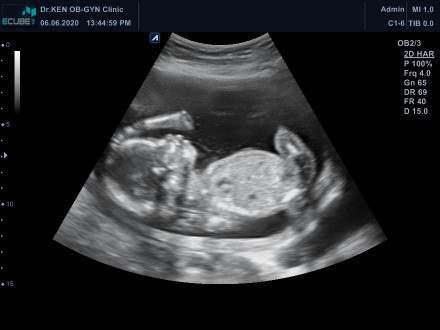

อยากเห็นใบซาวด์ทีมพฤศจิ😍

มาอวดกันเร็ววว🥰🥰 บ้านนี้13 พฤศจิ